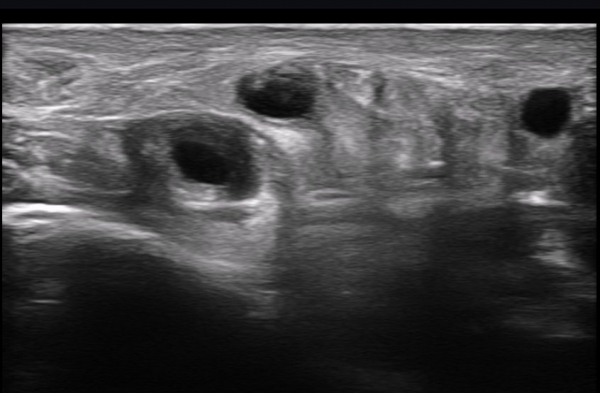

ÃÊÀ½ÆÄ ¼Ò°ß : ºñº¹½Å°æ Ⱦ´Ü¸é°Ë»ç¿¡¼­(»çÁø 1~13) ºñº¹½Å°æÀÇ Àú¿¡ÄÚ ºÎÁ¾°ú ´Üºñ°ñ°Ç³» ³¶Á¾¼º º´º¯ÀÌ °üÂûµÈ´Ù.

ºñº¹½Å°æ Á¾´Ü¸é°Ë»ç(»çÁø 14, 15)¿¡¼­ ºñº¹½Å°æÀÇ Àü¹ÝÀûÀÎ Àú¿¡ÄÚ ºÎÁ¾°ú ºñº¹½Å°æ ½ÉÃþÀ¸·Î ´Üºñ°ñ°Ç³»

³¶Á¾¼º º¯º¯ÀÌ °üÂûµÈ´Ù.